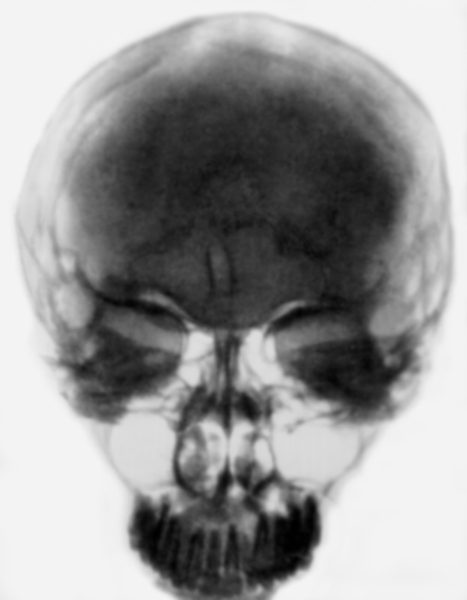

Рентгеновские снимки и визуализация болезни Педжета

Раздел: Мудрость в объективе